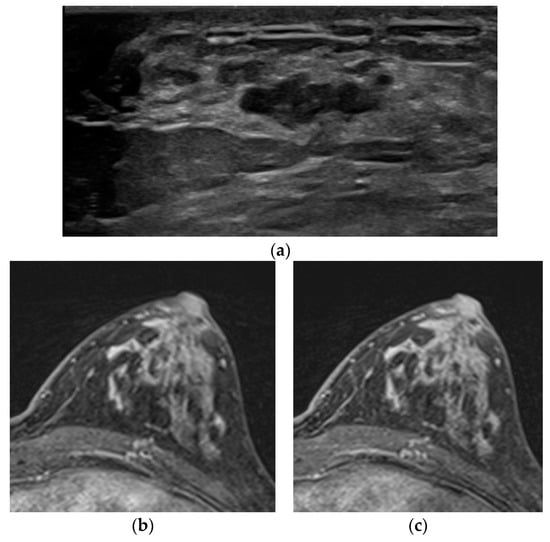

Figure 1. A 42-year-old woman with screening. (a) In the ultrasound, there was a 5.5 cm extent diffuse nonmass lesion at the right upper breast, and this lesion was confirmed as an invasive lobular carcinoma on core needle biopsy. (b) No discernible enhancing lesion at the right upper breast in the early phase of dynamic contrast-enhanced T1WI. (c) Also, no detectable enhancement at the correlating site in the contrast-enhanced chest CT.

Table 2 shows the imaging features and histology of 12 cases of not-detected malignancy in DCE MR and their main causes. Of these cases, 10 were detected by ultrasound and 5 by mammography. Six lesions were only seen by ultrasound and one lesion by mammography. In five cases (Nos. 1–5), lesions could not be distinguished because there was no or little enhancement due to non-enhancing histologic features; mucinous carcinoma (n = 3), ILC (n = 2) (Figure 1).

We defined and classified three main causes. The first is rare but known as not-enhancing histologic features. Mucinous carcinoma has abundant extracellular mucin secreted by tumor cells and shows high SI in T2WI. DCE MR is known to show various enhancement patterns depending on the distribution of solid and mucinous components; however, when mucin is predominant, there is almost no enhancement in some cases [14,15]. In our cases of mucinous carcinoma, lesions were not identified using DCE MR only but were identified after correlating with T2WI. However, since the T2WI feature of mucinous carcinoma, a well-circumscribed mass with T2 high SI, also overlaps with the benign feature, attention should be paid to MR interpretation [6,16]. ILC had a distinctive histologic feature of an “Indian File” growth pattern that diffusely infiltrates the adjacent breast parenchyma [17]. Perhaps because of this unique growth pattern, some lobular carcinomas might be able to receive a vascular supply through the diffusion of the preexisting parenchymal capillary network, which leads to less dependence on neovascularization [9]. In our cases of ILC, conventional imaging, such as mammography and ultrasound, was more useful in lesion detection.